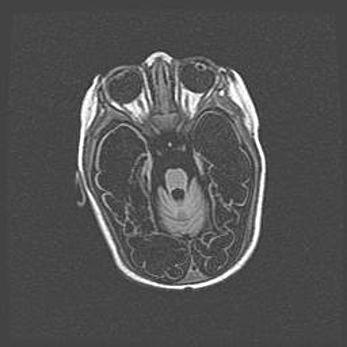

Церебральная ишемия II.

Возраст: 5 дней

Вес: 3400 г

Пол: женский

Окружность головы: 35 см

Срок гестации: 39 недель

Церебральная ишемия – это заболевание, характеризующееся недостаточностью (гипоксией) либо полным прекращением (аноксией) снабжения мозга кислородом по причине закупорки одного или нескольких сосудов. Это приводит к  что метаболическим расстройствам различной степени тяжести в тканях головного мозга, развитию коагуляционных некрозов и гибели нейронов.